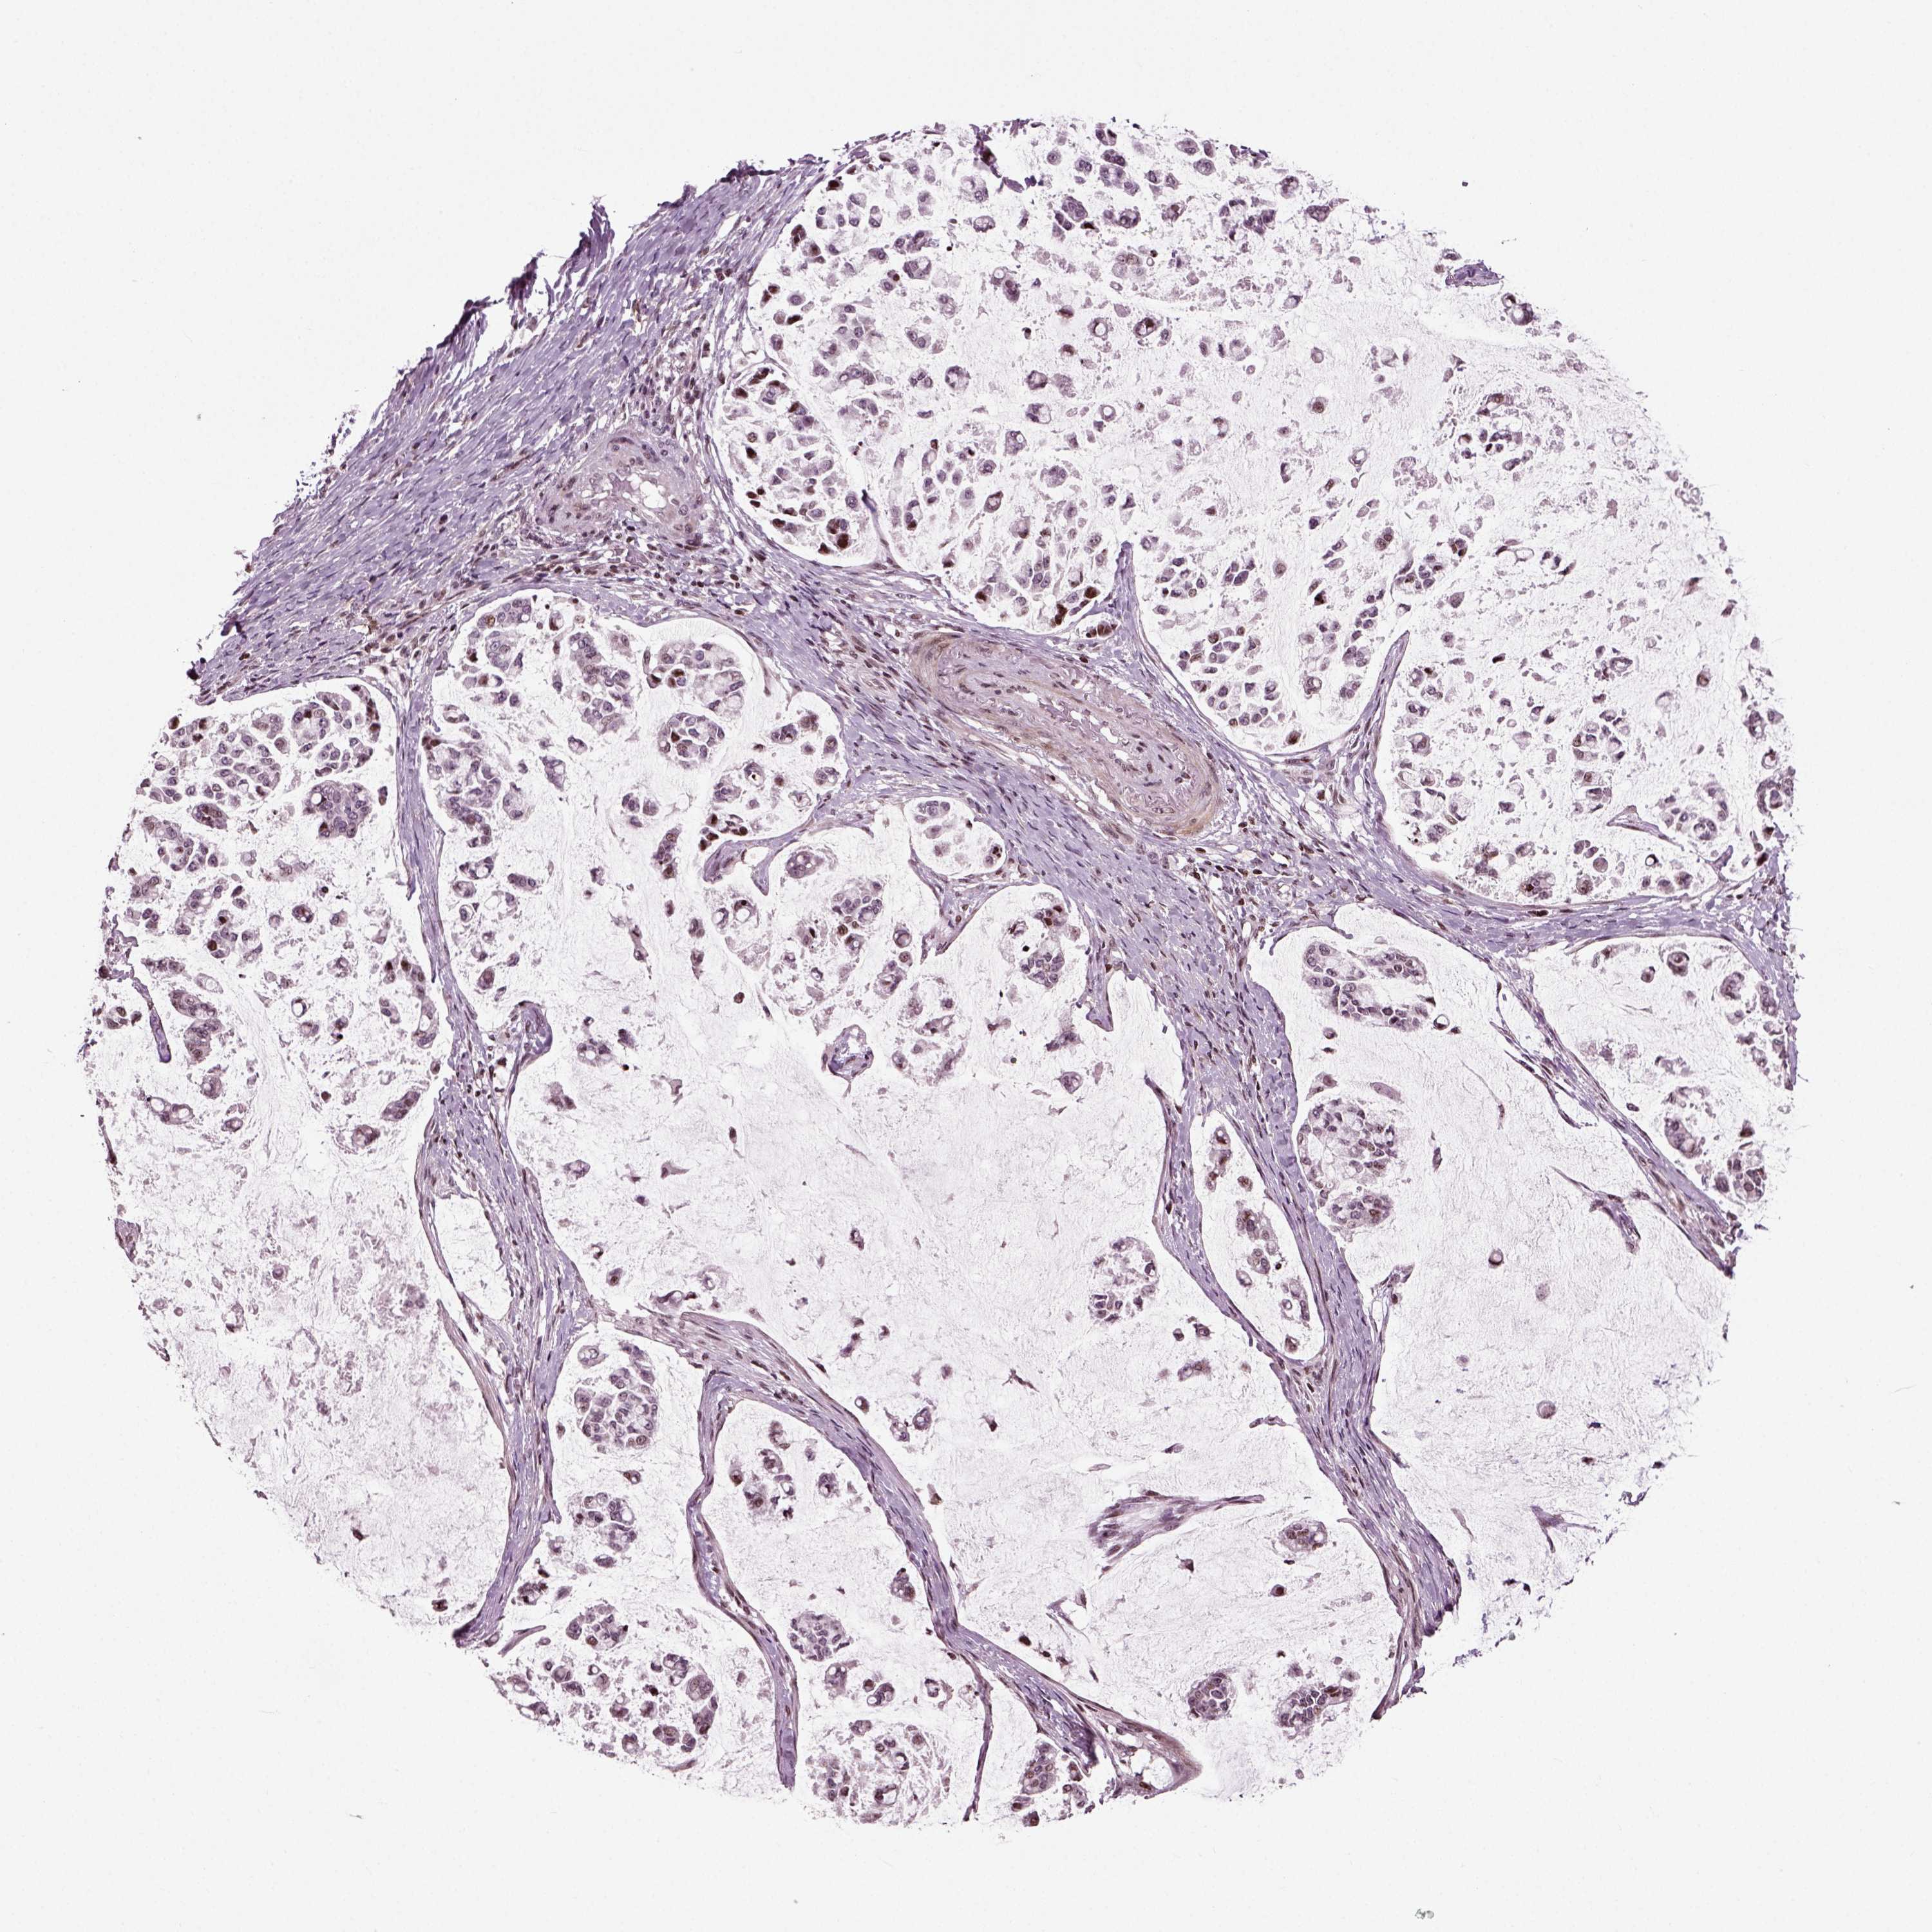

STOMACH CANCER - Protein expressioni

A mouse-over function shows sample information and annotation data. Click on an image to view it in a full screen mode. Samples can be filtered based on level of antibody staining by selecting one or several of the following categories: high, medium, low and not detected. The assay and annotation is described here.

Note that samples used for immunohistochemistry by the Human Protein Atlas do not correspond to samples in the TCGA dataset.

Antibody stainingi

Antibody staining in the annotated cell types in the current human tissue is reported as not detected, low, medium, or high, based on conventional immunohistochemistry profiling in selected tissues. This score is based on the combination of the staining intensity and fraction of stained cells.

Each image is clickable and will lead to virtual microscopy that enables deeper exploration of all samples and also displays staining intensity scores, fraction scores and subcellular localization as well as patient and tissue information for each sample.

Antibody HPA076960

Staining

High

Medium

Low

Not detected

Intensity

Strong

Moderate

Weak

Negative

Quantity

>75%

75%-25%

<25%

None

Location

Nuclear

Cytoplasmic/membranous

Cytoplasmic/membranous,nuclear

Adenocarcinoma, NOS